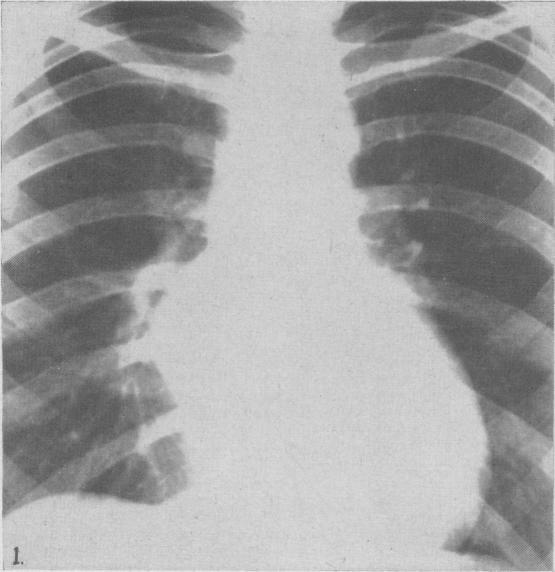

Ciliated columnar epithelial cyst of the mediastinum.

Can Med Assoc J. 1949 Nov;61(5):525-8.